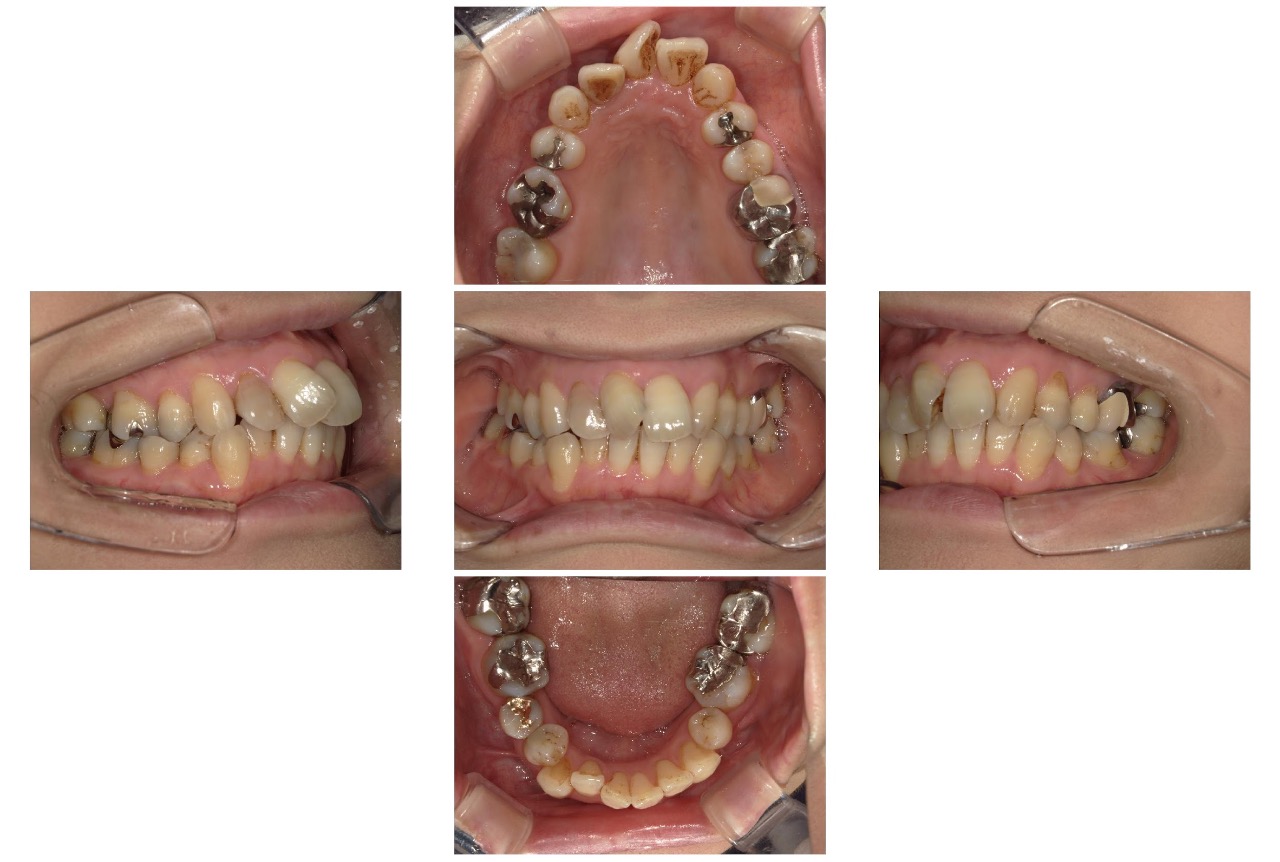

Case.02

治療前

治療後

| 主訴 | 上も下も凸凹してるのが気になる |

|---|---|

| 治療 期間 | 2年4カ月 |

| 治療費 | 880,000円 (税込968,000円) |

| 治療 内容 | インビザライン・顎間ゴム |

| 治療の リスク | 1日に20時間以上装着しないと、予定通りに歯が動かないことがあります。 装着後数日痛みがあります。 |